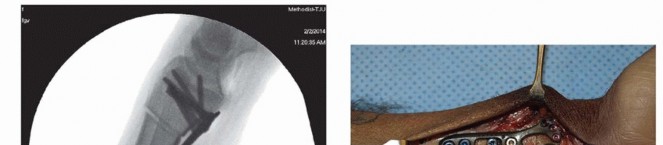

Osteotomy Execution and Radial Shortening

Now we arrive at the most critical step: determining the exact osteotomy level and executing the precise amount of shortening. Based on our preoperative templating, we require exactly 2.5 mm of shortening. We will perform a transverse osteotomy. While step-cut osteotomies offer inherent rotational stability, a transverse cut simplifies the precise calculation of shortening and allows for excellent compression when paired with a dynamic compression plate.

Image

We begin by placing two parallel